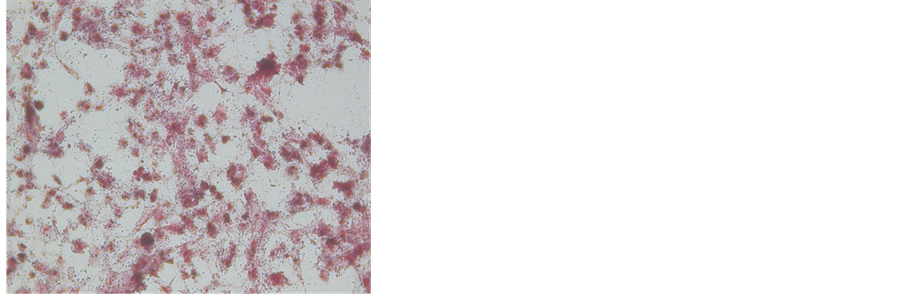

3.2. Identification of Osteoclast-Like Cells

As our previous study [14] , the osteoclast-like cells emerged three or more nuclei and pseudofoot-like activity at day 3. TRAP-positive multinucleated cells were observed at day 4. They were irregular or elliptical in configuration (Figure 1(d)).

Figure 1. (a) Osteoblasts cultured at 3d (×200). (b) ALP stained (×40). (c) Alizarin red stained (×200). (d) TRAP stained (×100). (e) Scanning electron microscopic picture of lacunae (×1400).

In bone resorption studies, many resorption pits are observed on a bone slice cultured with bone marrow cells at day 6. These bone resorption pits were round, oval, sausage, or irregular (Figure 1(e)).